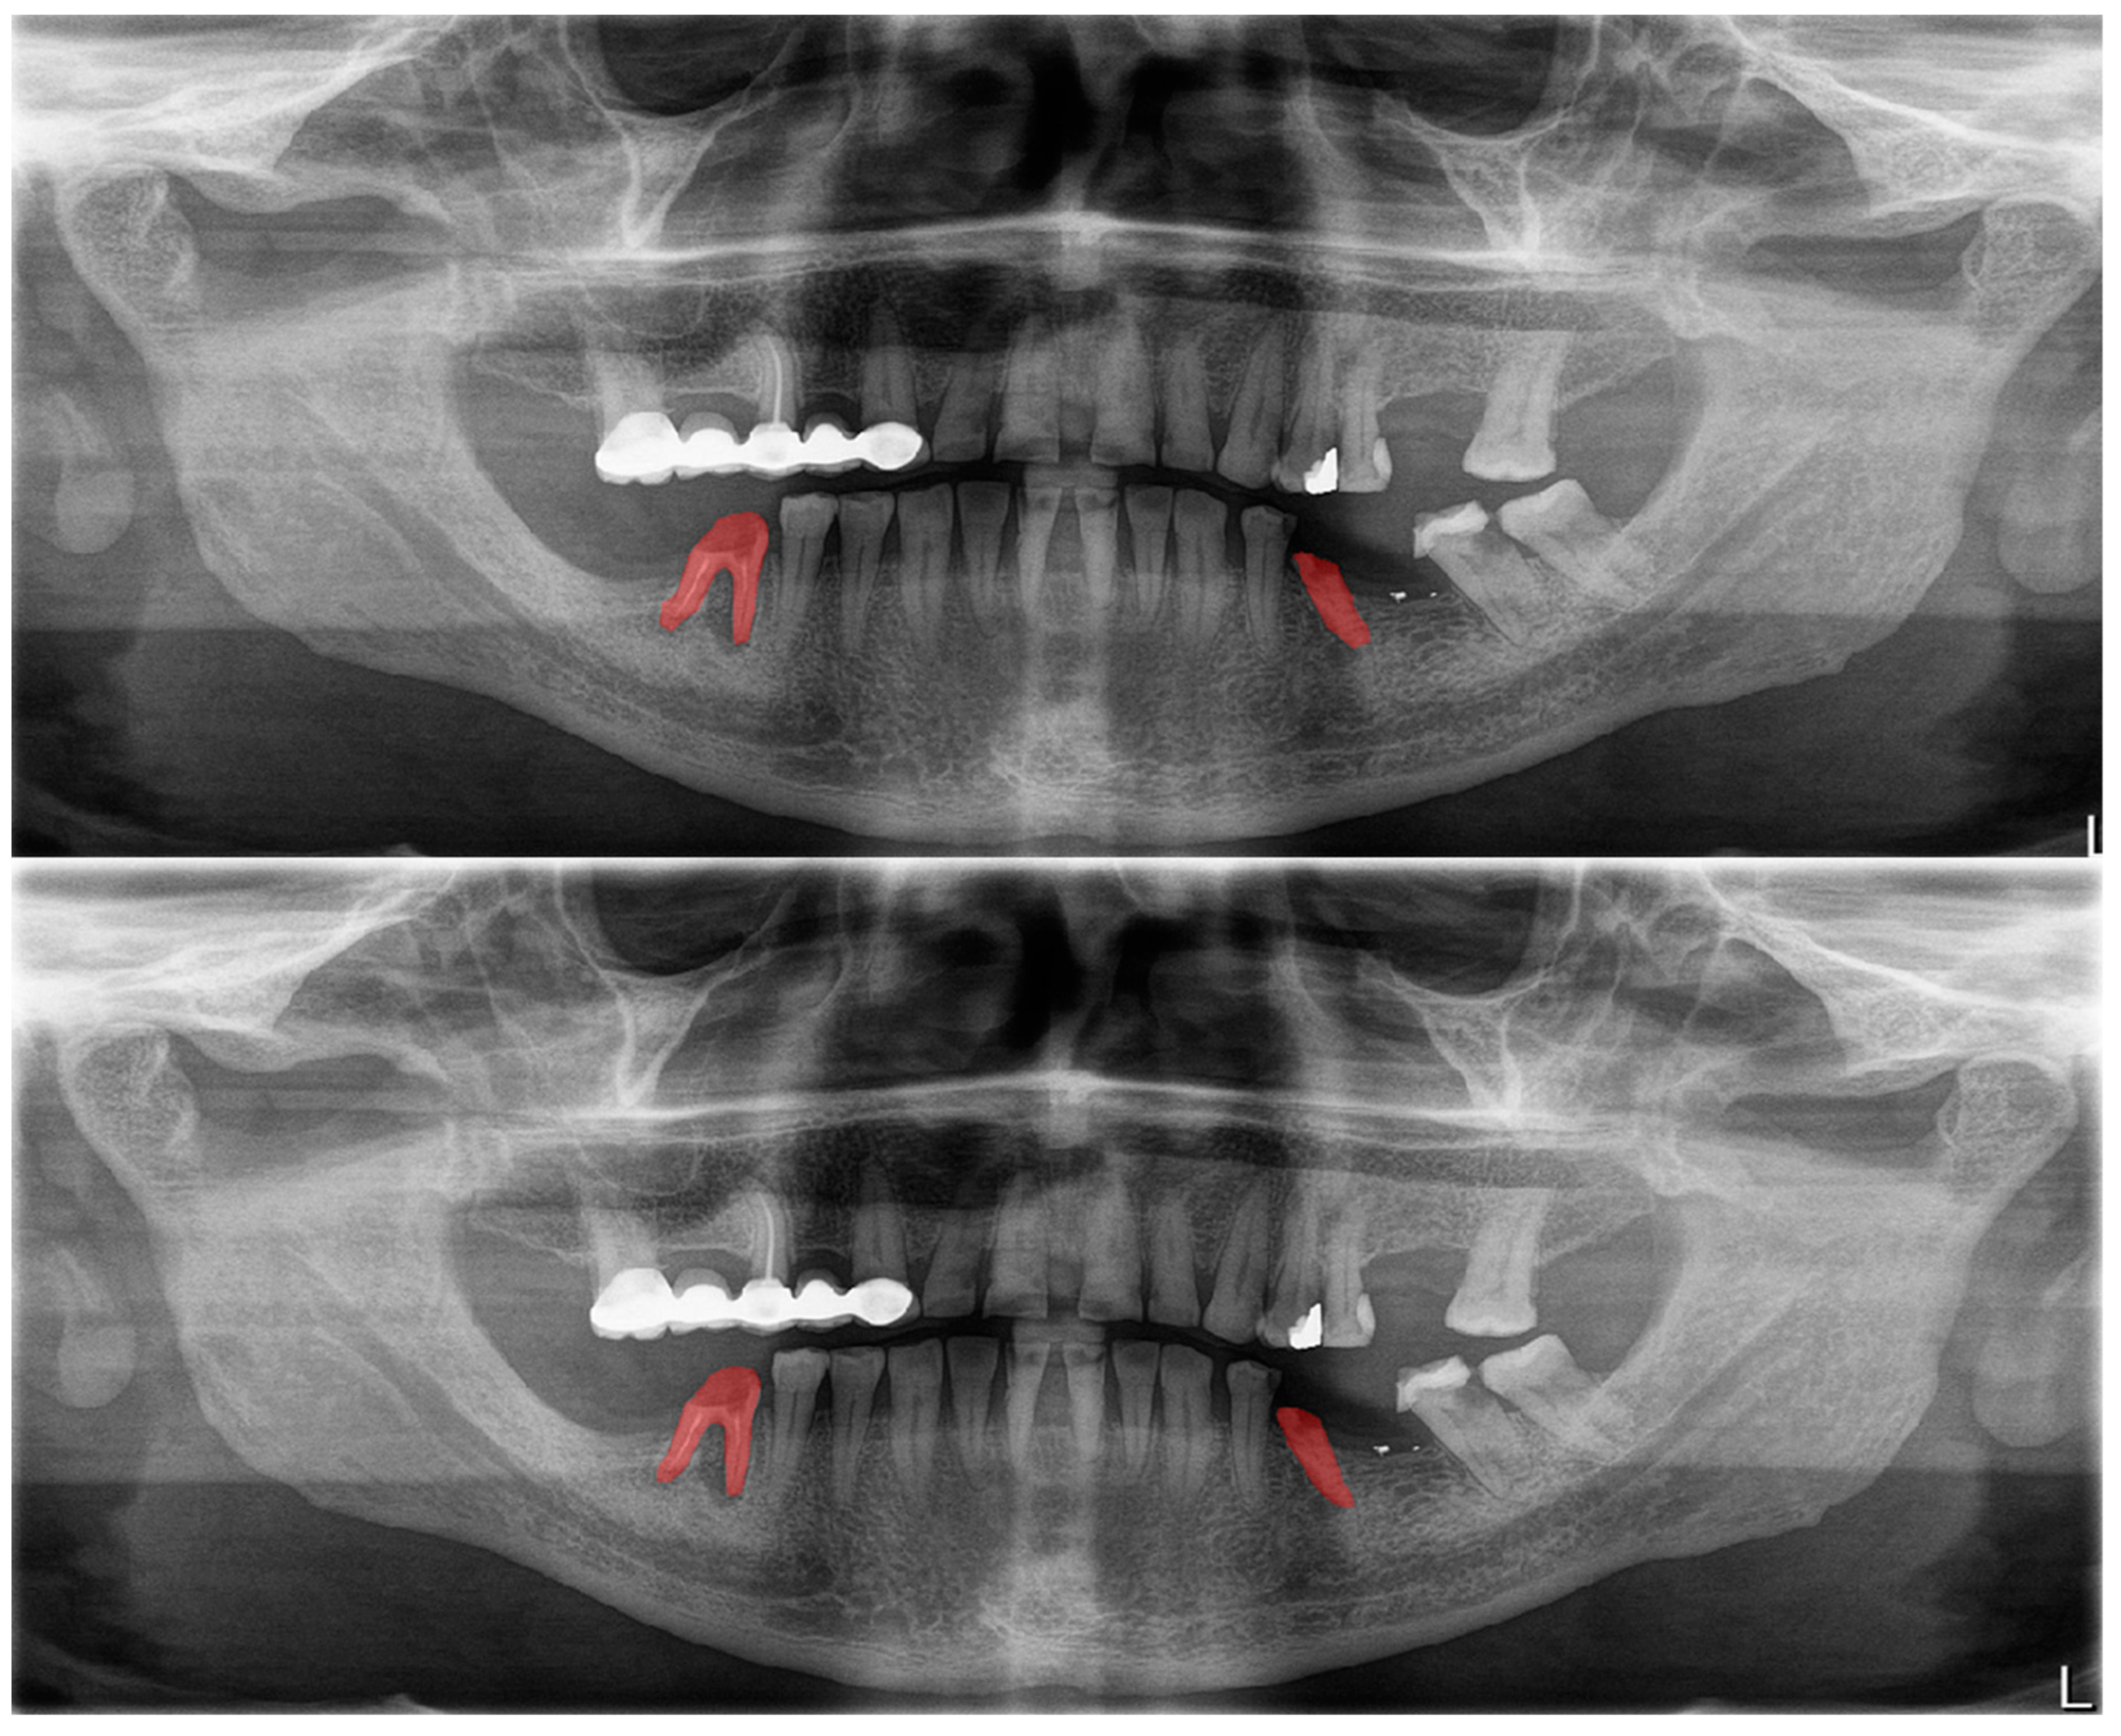

Figure 8.

Erroneous automatic segmentation at the maxillary left third molar due to the superimposition between the maxillary sinus floor and root apices of the tooth. Manual segmentation (upper image) and automatic segmentation (lower image) can be seen above.

Figure 9.

Erroneous automatic segmentation at the mandibular left second molar due to the superimposition between the mandibular left first and mandibular left second premolars. Manual segmentation (upper image) and automatic segmentation (lower image) can be seen above.

Figure 10.

A wide amalgam restoration in the mandibular left first premolar tooth was mis-segmented as a crown restoration. Manual segmentation (upper image) and automatic segmentation (lower image) can be seen above.

In Figure 8, a more successful automatic segmentation is observed at the maxillary right third molar than the maxillary left third molar, and a missing segmented area in the form of a notch is observed. As most of the upper third molars were superimposed on the floor of the maxillary sinus and zygomatic process of the maxilla, erroneous segmentations were inevitable. In Figure 9, an erroneous automatic segmentation at the mandibular left second molar due to the superimposition between the mandibular left first and mandibular left second premolars can be seen.

In Figure 10, it can be seen that a wide amalgam restoration in the mandibular left first premolar tooth was mis-segmented as a crown restoration. The mis-segmentation of wide amalgam restorations was seen in a total of five OPGs.